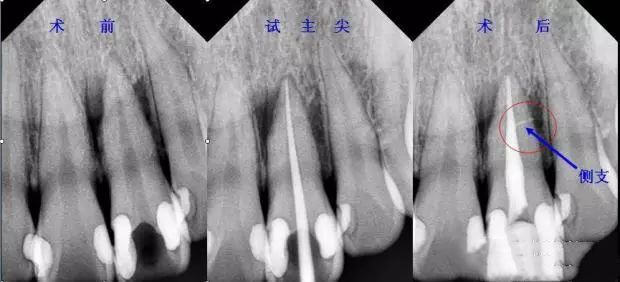

一 主尖选择原则

首选锥度等于或稍小于主锉,粗细型号等同于主锉,比如主锉首选6%25#,如果粗了选择6%20#,如果细了选择6%30#。主尖合适后在尖端3mm要有牵拉感,而且施加合适的力量主尖也不会超出狭窄部。